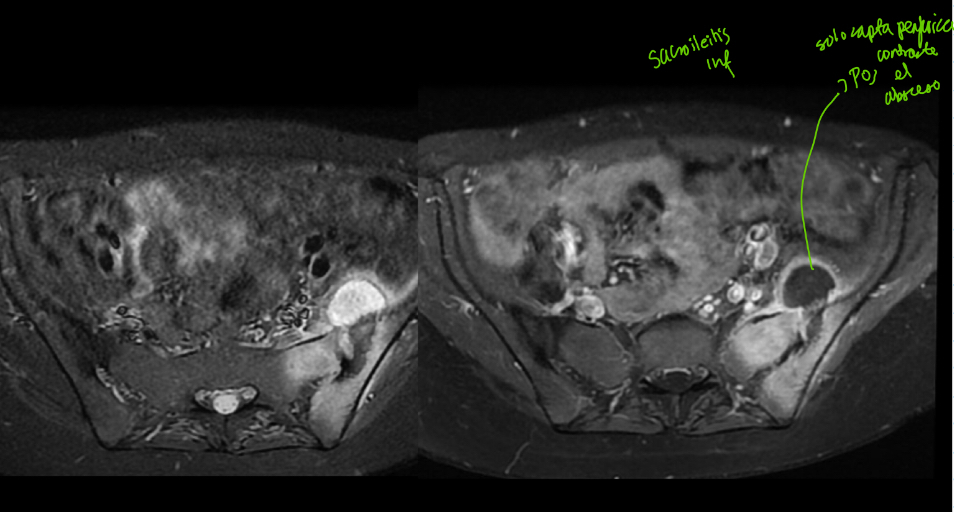

Q

q se ve en RM de sacroileitis

A

• lesiones peque

• Permite evaluar episodio agudo

• Evaluar involucro a otras estructuras

• Hiper en t2, fat sat, STIR

• Hipo t1

• Capta contraste

Q es

• sacroileitis infecciosa

• Solo capta contraste periferico

• Posible absceso